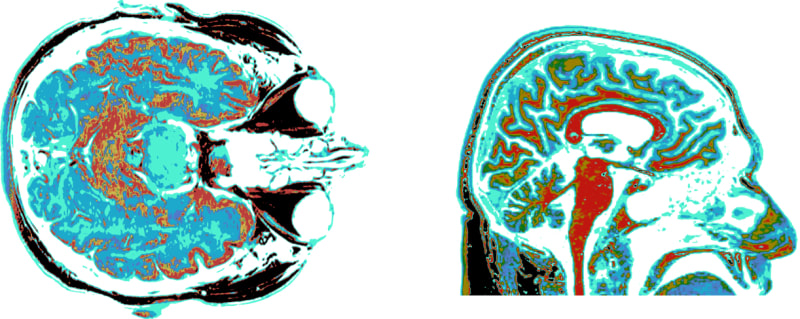

Stephen Wolfram examines the potential impact of larger brains on cognitive abilities, focusing on concepts, language, and computational reducibility. As neural networks grow, they may surpass human capabilities, revealing new capacities through increased neurons and connections. Abstraction and language evolve to manage complexity in thought, influenced by the brain's structure and computational principles. Larger brains could bring more concepts and refined models of the world, yet they face limitations inherent to computational irreducibility.